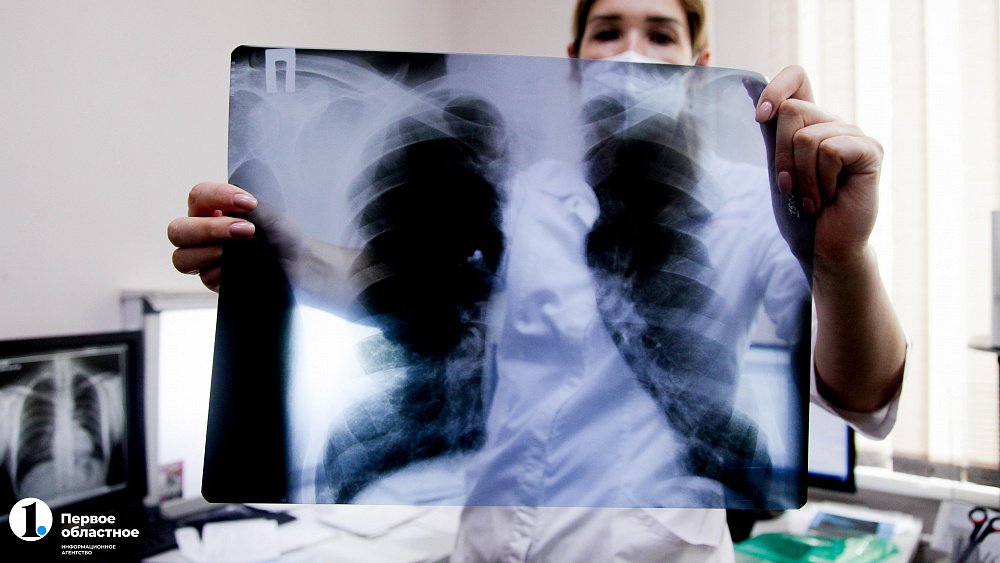

В Челябинской области с 1 августа начали проводить бесплатное углубленное обследование на туберкулез людей с ВИЧ-инфекцией. Помощь оказывается в рамках проекта «Зеленый коридор», выигравшего грант губернатора в размере 3 миллионов рублей. Обычная флюорография для диагностики заболевания у таких пациентов является неинформативной, поэтому им будут проводить обширный рентген грудной клетки и при необходимости отправлять на КТ. Об этом ИА «Первое областное» рассказали главный врач противотуберкулезного диспансера региона Марина Лехляйдер и руководитель общественной организации «Есть мнение» Юрий Авдеев.

«Порядка 40% вновь выявленных больных туберкулезом в Челябинской области — ВИЧ-инфицированные люди. Это наиболее уязвимая группа по заболеванию туберкулезом. Если у пациента с ВИЧ-инфекцией количество клеток CD4, которые отвечают за иммунитет, низкое, то есть 350 и ниже, он в 80% случаев заболеет туберкулезом. Это заболевание для таких пациентов смертельно и развивается иначе, чем у здоровых. И коварство в том, что обычный ФОГ даже не покажет, что человек болен», — рассказала Марина Лехляйдер.

Поэтому для вновь выявленных пациентов с ВИЧ-положительным статусом в Челябинской области в рамках проекта организовали незамедлительное обследование на туберкулез с помощью рентгенографии грудной клетки по системе «зеленый коридор». Для этого за человеком закрепляют специального куратора. Он буквально доводит человека до врача для незамедлительной диагностики, которая при необходимости будет включать в себя еще и компьютерную томографию.